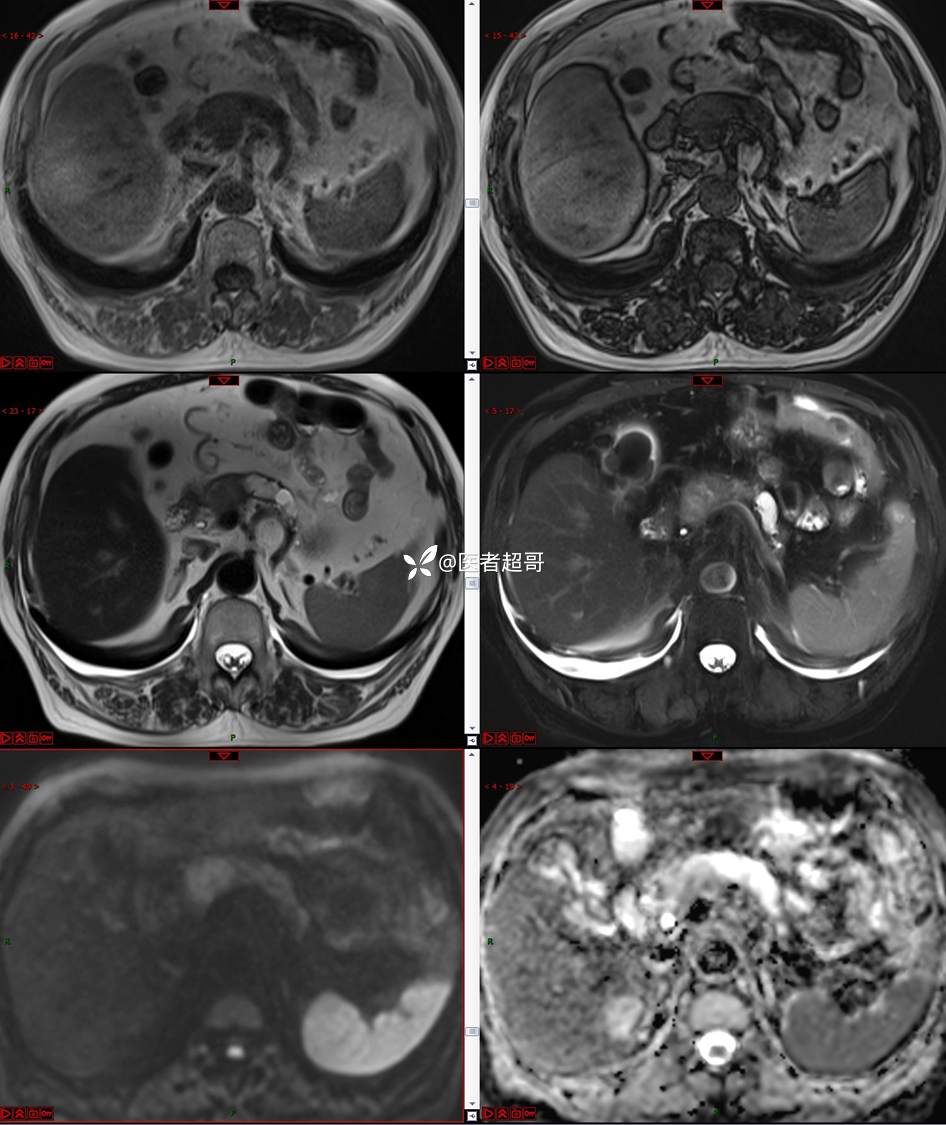

【影诊笔记677】查体发现胰腺占位性病变1周,细节决定成败,请诊断分析!

主 诉:查体发现胰腺占位性病变1周。

现病史:患者1周前在当地查体时发现胰腺占位性病变,无恶心、呕吐,无腹痛,无寒战、高热,无咳嗽、咳痰等异常不适,来我院门诊查上腹部CT平扫+强化:胰腺尾部异常密度灶。今为求进一步治疗,门诊以“胰腺占位性病变”收入院。患者自发病以来,一般情况可,神志清,精神可,普通饮食,二便正常,体重及体力无明显改变。

既往史:既往糖尿病病史2年,口服二甲双胍早晚各一片和格列吡嗪早晚各一片,否认高血压、心脑血管病等疾病史,否认肝炎、结核或其他传染病史及密切接触史,预防接种史不详,否认药物及食物过敏史,否认外伤史,12年前肾癌切除术手术史,否认输血史,其它无特殊。